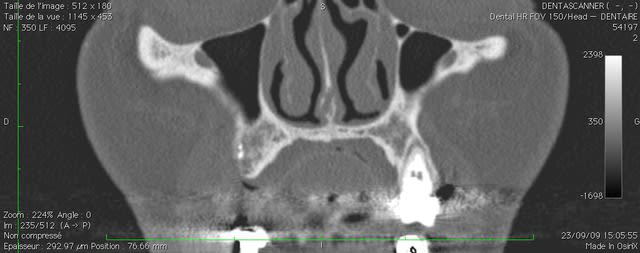

oui ça fait un gros prélèvement, c'est pour un cas particulier ou je dois virer 24, 25 et 26 avec de grosses lésions apicales et latérales, ou je voudrais conserver le maximum de volume osseux pour pouvoir implanter dans de bonnes conditions.

ci joint la pano et les coupes scan.